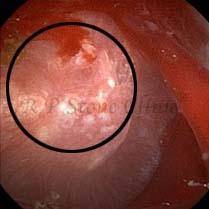

Kidney stone is a solid mass of CRYSTALS. It is the process of crystallization which initiates the formation of kidney stones. This happens in nephrons or units of kidney. Once a small crystal is formed, it can both grow & unite with other crystals leading to the formation of small concretion which eventually forms a stone. Once these large crystals detach from the collecting ducts, the process of stone formation starts in the renal collecting system. A recurrent kidney stone former is advised to know a little bit about something known as Randall’s plaque. Alexander Randall discovered plaques on the renal papillae eight decades back based on examination of 1154 pairs of autopsied Kidneys. He described these renal papillary lesions as cream colored or milk patch areas composed of calcium phosphate & calcium carbonate. These plaques could act as NIDUS for formation of KIDNEY STONE. Calcium Oxalate stone can form on this nidus & then detaches from this plaque to become a free floating stone in the collecting system of kidney

These images are taken as snap shots from the video recording of RIRS Surgery done at our hospital. These are Randall’s Plaques seen with Digital FLEX XC & Digital FLEX XC S. The cream or whitish patches are seen on the tips of RENAL PAPILLAE as seen in images below.

Randall’s Plaques may lead to the formation of Stones.

Those kidney stone patients who have Randall’s Plaques in their kidneys are more likely to form stones again (Recurrent Stones).

Stone Patients in whom Randall’s Plaques are detected at the time of RIRS Surgery should undergo regular ultrasound examination for early detection of stones.

Patients of Stones with Randall’s Plaques in their Kidneys should drink plenty of fluids in addition to Orange Juice & Lemonade.